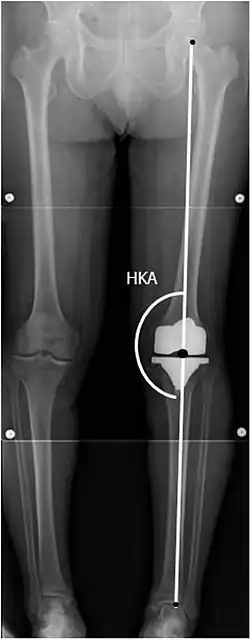

![]() |

Angles commonly measured before knee replacement surgery: |

To indicate knee replacement in case of osteoarthritis, its radiographic classification and severity of symptoms both should be substantial. Such radiography should consist of weightbearing X-rays of both knees: AP, lateral, and 30 degrees of flexion. AP and lateral views may not show joint space narrowing, but the 30-degree flexion view is most sensitive for narrowing. Full-length projections also are used in order to adjust the prosthesis to provide a neutral angle for the distal lower extremity. Two angles used for this purpose are:

- Hip-knee-shaft angle (HKS),[14] an angle formed between a line through the longitudinal axis of the femoral shaft and its mechanical axis, which is a line from the center of the femoral head to the intercondylar notch of the distal femur.[16]

- Hip-knee-ankle angle (HKA),[15] which is an angle between the femoral mechanical axis and the center of the ankle joint.[16] It is normally between 1.0° and 1.5° of varus in adults.[17]